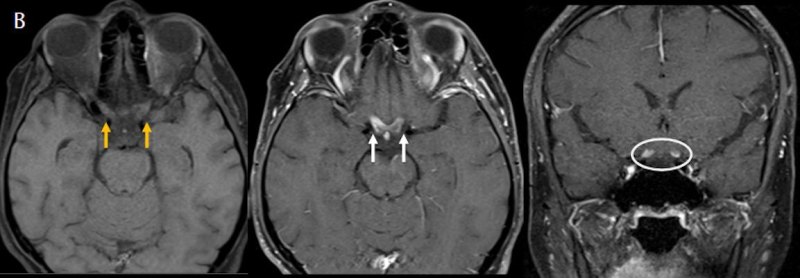

- (B) Orbita MRG’de aksiyel yağ baskılı T1A’da optik sinir prekiazmatik segmenti (oklar) gösterilmiş olup sırası ile aksiyel ve koronal post-kontrast yağ baskılı T1A görüntülerde bilateral optik sinir prekiazmatik segmentte kontrast tutulumu dikkati çekmektedir (oklar ve daire).

- Optik nörit varlığında özellikle optik kiazma ve posterior optik sinir tutulumu görülür ve bilateral olabilir.

- MS’de optik nörit radyolojik tutulumu daha fokal iken NMO spektrum bozukluğu ve MOGAD’de genellikle daha yaygındır. MOGAD, NMO’ya kıyasla daha anterior kısmı etkileme eğilimindedir.